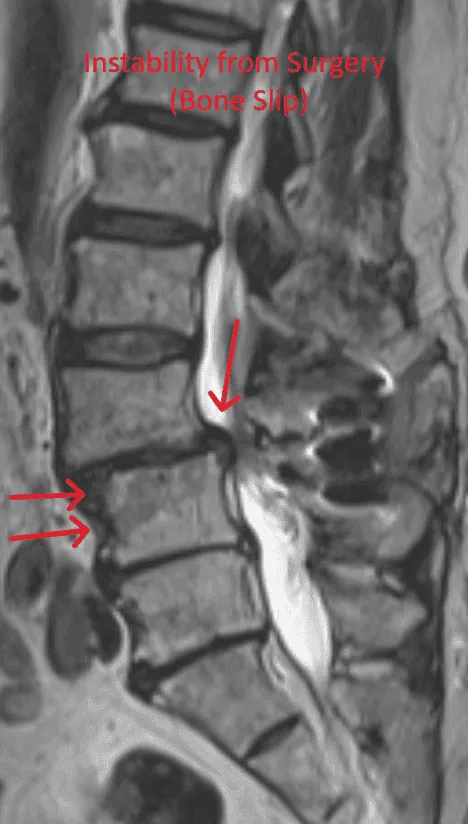

MRI scan highlighting spinal instability and bone slip with red arrows and text.

Spinal Instability

Laminectomy during placement removes stabilizing structures, causing instability requiring fusion with screws and rods.